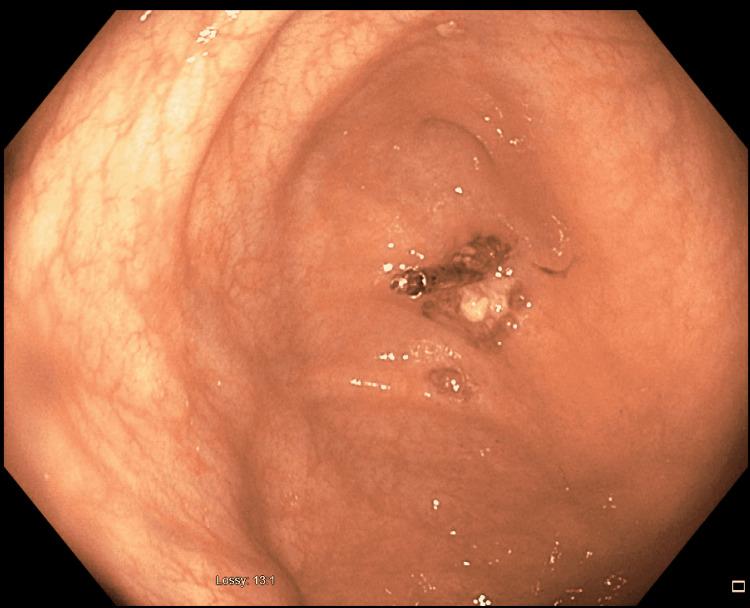

Splenic injury is usually seen with penetrating or blunt abdominal trauma. It is also one of the rare complications of colonoscopy. Various patient and procedural factors have been reported to increase the risk of this dreaded complication. We present a case of splenic injury after outpatient colonoscopy where intra-abdominal adhesions from previous abdominal surgeries were presumed to be the cause of splenic injury. Our patient had improved outcomes with timely diagnosis and intervention.

脾损伤通常见于腹部穿透伤或钝性伤。它也是结肠镜检查罕见的并发症之一。据报道,多种患者因素和操作因素会增加这种可怕并发症的风险。我们报告一例门诊结肠镜检查后发生脾损伤的病例,推测既往腹部手术导致的腹腔粘连是脾损伤的原因。我们的患者通过及时诊断和干预,预后良好。